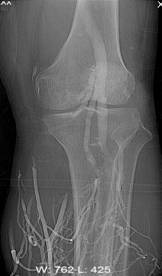

何××,男,6岁,儿童股骨头坏死,左侧股骨头骨骺坏死、骨质碎裂(图3),经治疗后骨骺骨质恢复(图4)。

图3 图4